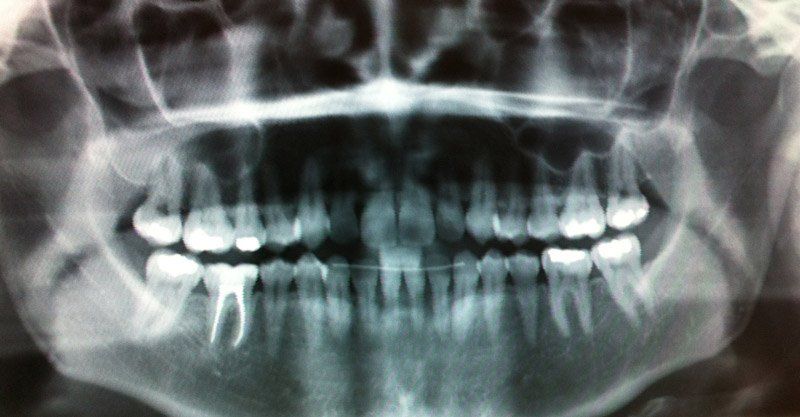

ORTHOPAN RÖNTGENMYNDATÆKIÐ

Stafrænar Orthopan- og sneiðmyndir

Hjá Krýnu er orthopan röntgenmyndatæki ORTHOPHOS PLUS frá Sirona sem einnig gefur möguleika á sneiðmyndum.

Myndirnar eru á stafrænu formi sem gerir kleift að stækka, auka/minnka þéttleika og skerpu.